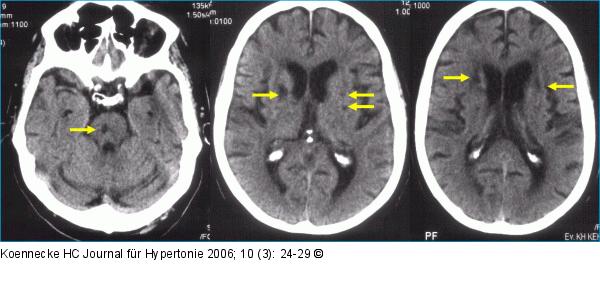

Abbildung 1a: Zerebrale Mikroangiopathie - Arterielle Hypertonie Zerebrale Mikroangiopathie infolge langjähriger arterieller Hypertonie. Kranielles Computertomogramm eines Patienten mit multiplen lakunären Infarkten (Pfeile) im Bereich von Pons (links), Stammganglien (Mitte) und periventrikulärem Marklager (rechts) |

Zerebrale Mikroangiopathie infolge langjähriger arterieller Hypertonie. Kranielles Computertomogramm eines Patienten mit multiplen lakunären Infarkten (Pfeile) im Bereich von Pons (links), Stammganglien (Mitte) und periventrikulärem Marklager (rechts) |